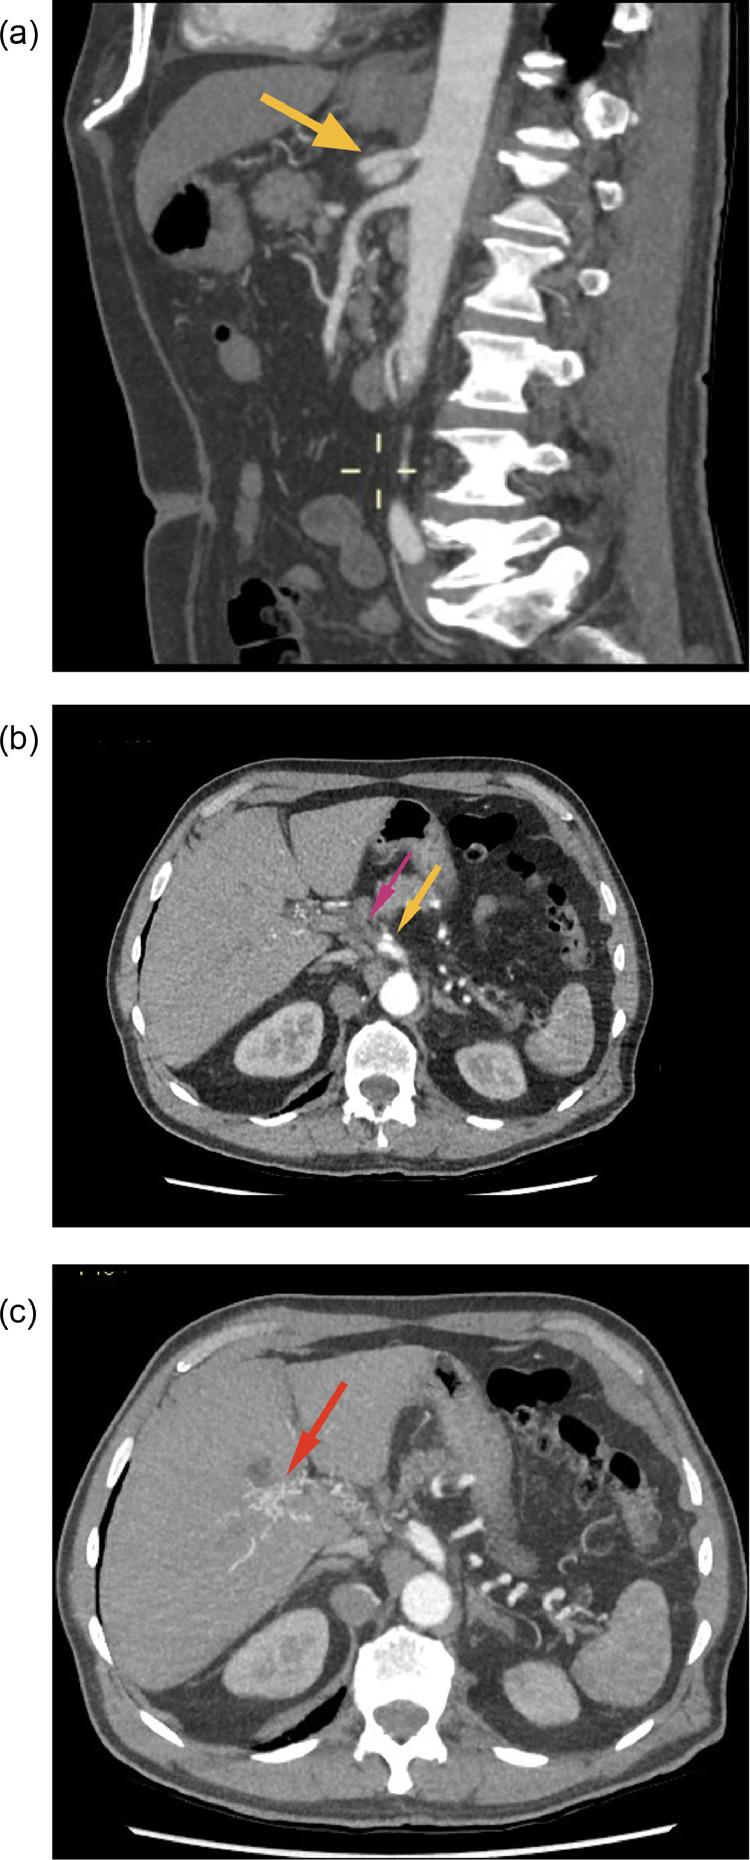

Isolated celiac artery dissection (ICAD) is a rare entity with over 160 cases described in literature. We report a case of incidentally detected isolated celiac artery dissection during computed tomography evaluation for occult gastrointestinal bleeding. Though most cases of isolated celiac artery dissection are initially managed conservatively with antiplatelet and anticoagulants, some patients may require endovascular or occasionally surgical treatment. In our case, the celiac artery dissection had already progressed to cause hepatic artery occlusion and secondary collateral formation in the porta hepatis region. We retrospectively analyze the natural course of celiac artery dissection with hepatic artery occlusion in an asymptomatic patient for over 3 years.

孤立性腹腔干动脉夹层(ICAD)是一种罕见疾病,文献中描述的病例超过160例。我们报告了1例在针对隐匿性胃肠道出血进行计算机断层扫描评估时偶然发现的孤立性腹腔干动脉夹层。虽然大多数孤立性腹腔干动脉夹层病例最初采用抗血小板和抗凝药物进行保守治疗,但一些患者可能需要血管内治疗或偶尔进行手术治疗。在我们的病例中,腹腔干动脉夹层已经进展,导致肝动脉闭塞和肝门区继发性侧支形成。我们回顾性分析了1例无症状患者腹腔干动脉夹层伴肝动脉闭塞超过3年的自然病程。